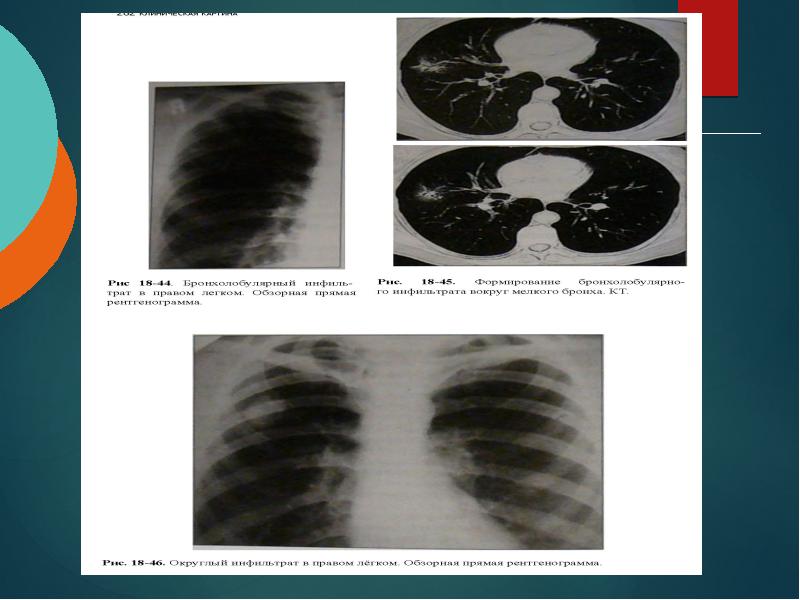

Очаговый и инфильтративный туберкулез презентация - 94 фото